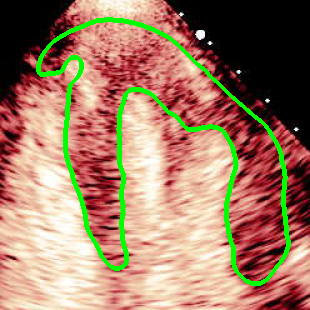

For variations caused by low quality images such as those of low resolution or significant artifacts, however, the unique ground truth may not be available. Take the myocardial segmentation task of Myocardial Contrast Echocardiography (MCE) as an example. An inter-observer experiment was conducted among five experienced cardiologists, and Fig. 1(a)(b) visualize the annotations of two images from three of these cardiologists. It can be seen that the labels by different cardiologists vary significantly, especially in locations where the intensity information of myocardium is very similar to the background. Table 1 shows the average Dice of the annotation of each cardiologist, using one of the others’ as the ground truth, over 180 images. We can observe that none of the Dice is above 0.9, some even under 0.8, confirming significant variations among the annotations. In this case, as the variations are caused by the image quality, even these cardiologists cannot tell which annotation is better than others, and a majority vote for ground truth would not make sense sometimes as can be seen in Fig. 1(c)(d). For this reason, we cannot obtain a unique ground truth in the evaluation process and the traditional metrics such as Dice and IoU cannot be used.